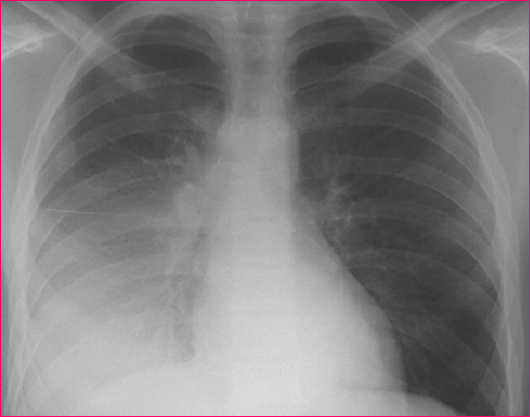

大叶性肺炎

(lobar pneumonia)

16岁患者患大叶性肺炎:

胸部 X 线检查所见:右下中

叶片状阴影,向基底部密度

增加